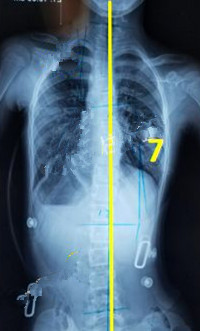

一般經(jīng)過三個月至六個月的治療,對稱度都能得到改善,力線回正。

此時(shí)由于患者已經(jīng)完全適應(yīng)支具的力點(diǎn),且體表變化較大,為了進(jìn)一步矯正,我們需要對支具進(jìn)行調(diào)整。如果由于孩子身高的變化較大,為了更進(jìn)一步的矯正,可以考慮更換新的支具。

穿支具后